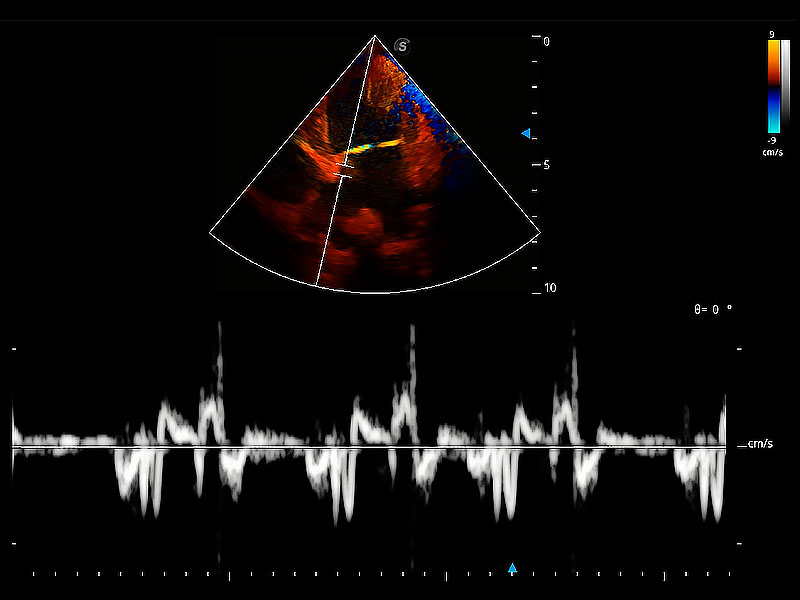

實(shí)時(shí)用顏色表示心肌組織運(yùn)動(dòng),觀察和定量組織的運(yùn)動(dòng)情況,對(duì)快速檢測(cè)與評(píng)估心肌的灌注和活性、電傳導(dǎo)及心肌收縮和舒張功能等均能提供重要的診斷信息。

ProPet 80 配備了豐富的心臟探頭群、先進(jìn)的成像技術(shù)和專業(yè)的心臟測(cè)量工具,可幫助動(dòng)物醫(yī)生為不同體型和生理結(jié)構(gòu)的動(dòng)物提供心臟和心肌功能的全面評(píng)估。